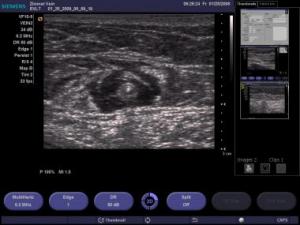

The selection of candidates for ELA involves a directed history, physical examination, and duplex ultrasound (DUS) examination.